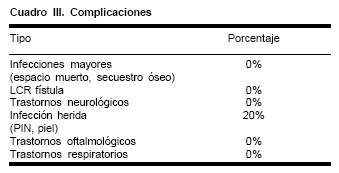

Las complicaciones en esta serie clínica se ven limitadas a la presencia de infecciones de la piel cabelluda en el sitio de salida del distractor en 20% de los pacientes, lo que resolvió con antibióticos y limpieza local. Abscesos intracraneanos, secuestros óseos, graves infecciones, graves infecciones por contaminación por la vía aérea, fístulas de líquido cefalorraquídeo, convulsiones u otras alteraciones neurológicas, no se han observado en este grupo de pacientes (Cuadro III).

Además, el número de complicaciones disminuye en forma muy importante, cuando se compara con las técnicas convencionales (Cuadro III). Es sorprendente cómo todos estos pacientes toleran llevar los distractores y la mínima cantidad de molestias que refieren durante la activación de los mismos durante el proceso óseo. El hecho de no crear espacios muertos intracraneanos evita infecciones y secuestros óseos, la asistencia endoscópica verifica hemostasia y produce una disección de las meninges más cuidadosa, lo que evita desgarros y fugas de líquido cefalorraquídeo. Este detalle es particularmente importante en los avances en "monobloque", debido a que no se producen comunicaciones entre el espacio intracraneano y la vía aérea.